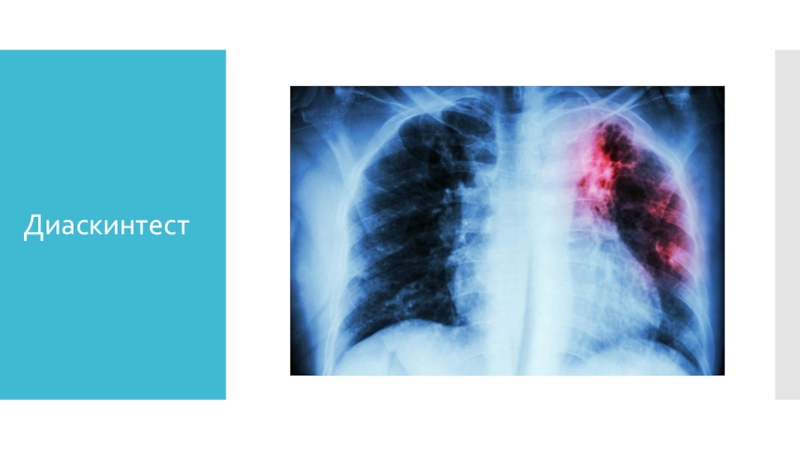

Слайд 5Диаскинтест

Диаскинтест